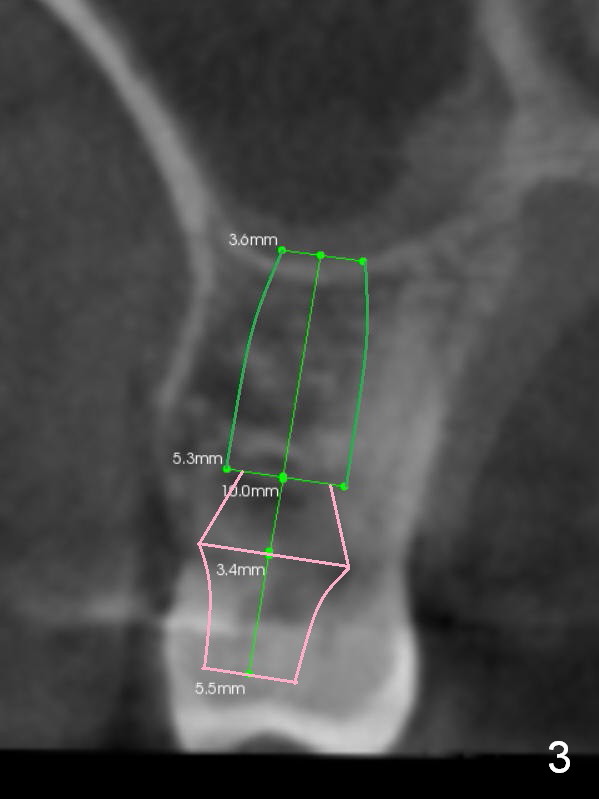

In addition to supraeruption of the teeth #2 and 3, the caries in the mesiobuccal root of #3 seems to be beyond salvation (Fig.1,2 arrowhead). When the implant at #3 is osteointegrated, a provisional restoration is placed (Fig.4 pink). Brackets (white boxes) are placed at differential levels among #1-3 to initiate regional orthodontic treatment using #3 as an anchorage. Mini-implants are placed if necessary. The tooth #1 is extracted after the limited ortho. Scaling & root planing will be done first.

Re-examination clinically and radiologically reveals that there is no caries involving the tooth #3 (Fig.5). It appears that CBCT may have artifact. Treatment planning for intrusion should be modified. Mini-implants will be employed after #2 DO composite. Prepare Anchor mini-implant kit, 2 of 10 mm and 1 of 8 mm mini-implants, anesthetics and #15 scalpel. Scaling & root planing will be performed.